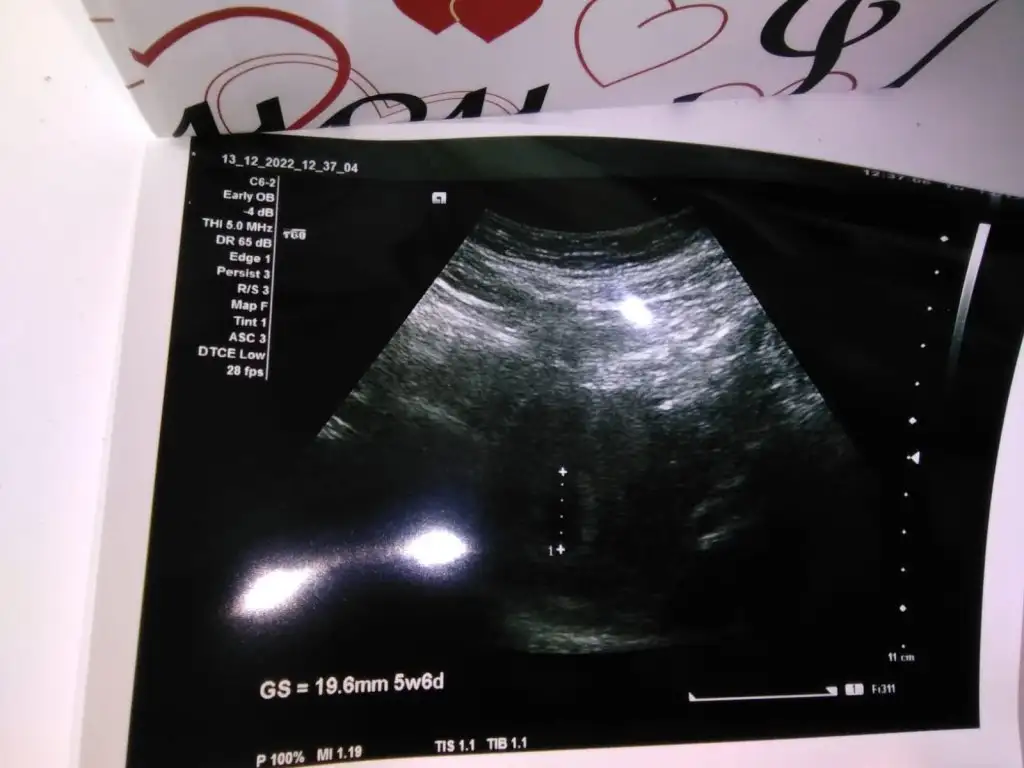

Vajinelse kız karındansa erkekEki Görüntüle 3209108 7 haftalık teşekkür ederim

6-9 Haftalık ultrason görüntüsü yollarsanız bakayım böyle bilemiyorum maalesef nub anlamıyorumMerhaba banada bir tahminde bulunabilirmisiniz. Teşekkürler 15 haftalık Eki Görüntüle 3208672

6-8 haftalık ultrason fotosu varsa atın yorumlayayım burda bebek büyük, plesanta anlaşılmıyor10 haftalık bizede bakabilirmisinizEki Görüntüle 3210511